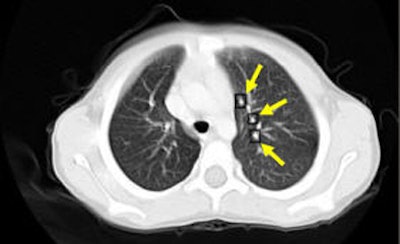

![]() |

| An example of successful nodule classification. Above, bright well-formed true nodules marked inside circles. Below, very similar non-nodule objects marked inside rectangles. The hybrid FP reduction stage accurately categorizes these objects as false positives. |